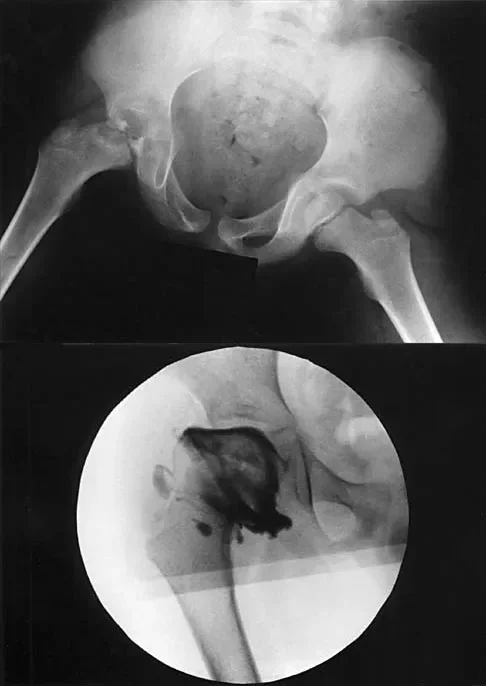

A 7-year-old boy with a history of a painless limp is diagnosed with Legg-Calvé-Perthes disease. An arthrogram is performed to evaluate joint congruency. The maximum abduction/internal rotation view is shown in Figure A, and the abduction view is shown in Figure B. The failure of the lateral epiphysis to slide under the acetabular edge with abduction, accompanied by medial dye pooling, is pathognomonic for which of the following conditions?

Explanation

Correct Answer: Hinge abduction

The arthrogram images demonstrate classic hinge abduction, a critical finding in severe Legg-Calvé-Perthes disease. Hinge abduction occurs when the enlarged, deformed lateral portion of the femoral head extrudes and impinges against the lateral margin of the acetabulum during abduction. Instead of gliding smoothly into the acetabulum, the femoral head hinges on the acetabular rim, causing the medial joint space to widen (distract), which is visualized as medial dye pooling on the arthrogram. Persistent hinge abduction prevents normal spherical remodeling of the femoral head and is an indication for surgical intervention to restore congruency.

A 7-year-old boy with a history of a painless limp undergoes an arthrogram of the hip, as shown in the provided images. The failure of the lateral epiphysis to slide under the acetabular edge during abduction is diagnostic of which of the following?

The arthrogram demonstrates hinge abduction, a severe complication of Legg-Calvé-Perthes disease where the deformed, extruded lateral portion of the femoral head hinges against the lateral acetabular margin during abduction, preventing concentric reduction. This persistent hinge abduction prevents femoral head remodeling by the acetabulum.

A 7-year-old boy with a history of a painless limp presents with limited abduction and spasm on internal rotation. Radiographs obtained during an arthrogram are shown. The failure of the lateral epiphysis to slide under the acetabular edge during abduction is diagnostic of which of the following?

Correct Answer: B

The radiographs demonstrate classic hinge abduction in a patient with Legg-Calve-Perthes disease. Hinge abduction occurs when the enlarged, deformed lateral portion of the femoral head impinges on the lateral acetabular margin during abduction, preventing the head from sliding concentrically into the acetabulum. The arthrogram shows medial dye pooling due to distraction of the joint. Persistent hinge abduction prevents proper femoral head remodeling and is an indication for surgical intervention.